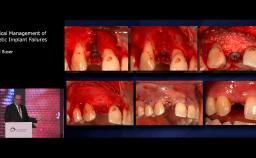

Extraction Site Bone Graft and Immediate Implant Placement in the Esthetic Zone

Patient expectations continue to increase, with the majority of patients expecting to have immediate replacement of missing teeth. This lecture provides a sound understanding of the key factors surrounding immediate implant placement. Advantages and disadvantages of this approach are discussed, using various cases to illustrate key points. Factors influencing esthetic outcome are discussed, with a good selection of evidence based information being presented.